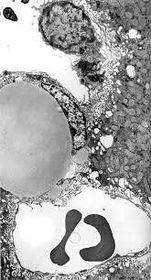

TEM of a part of the liver

A : large fat droplet inside Ito cell B : Kupffer cell C : Blood sinusoid D : Space of Disse E : Microvilli

A : Hepatocyte B : Kupffer Cell C : fat droplets inside Ito cell E : Space of Disse